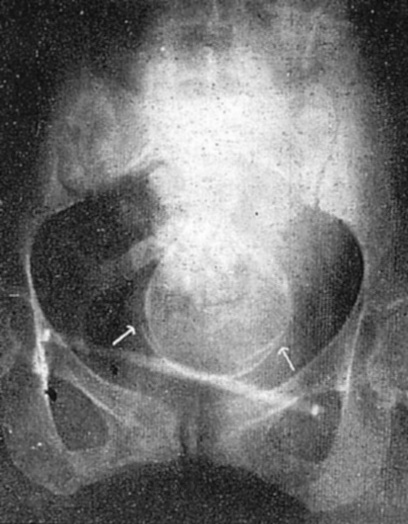

図7.骨盤内臓器の気腹撮影.a:子宮筋腫, b:円靭帯,c:有茎性筋腫 [24]

腹腔内にガスを注入することにより臓器の輪郭を描出する気腹法(pneumoperitoneum)は,1902年にKellingが腹腔鏡の補助手段として動物実験で試みているが[18],これを実験動物ではあるがX線診断に初めて応用したのは1913年Weberで[19], 1914年にはLorey[20], Rautenberg[21]がそれぞれ独立に臨床例を報告している.なお1921年にはCarelli[22]とRosenstein[23]がこれを後腹膜に応用して,腎の描出に成功している.

1918年,骨盤内臓器のX線診断に初めて気腹を応用したのはOtto Goetzeで[→原著論文],翌年にはアメリカのSteinらも子宮筋腫の例を報告している[24](図7).当初は空気や酸素が使用され気体塞栓症の危険が懸念されたが,1921年にAlvarezが吸収されやすい炭酸ガスを導入し[25],比較的安全に行えるようになった.

図9. 気腹撮影による正常骨盤像(側臥位,画面右が尾側).b:恥骨結合,c:子宮,d:広間膜

【要旨・解説】人工気腹によるX線診断の有用性を初めて本格的に報告した論文.本文中にも引用されているRautenbergの試みなど,これ以前にも気腹法の報告はあるがいずれも少数の限定的な対象に限られていた.外科医のGoetzeは,腹腔臓器のさまざま疾患について広くこれを応用し,骨盤内臓器にも初めて言及している.

技術的には,穿刺針が腹腔内臓器を損傷しないような穿刺針を工夫している.2~3Lの空気を注入し,空気が上部に貯溜することを利用して,さまざま体位で撮影することが重要である.骨盤腔の撮影では,膝肘位など骨盤を高位とする.妊娠,子宮筋腫,卵巣腫瘍などを診断できたとしている.提示されている画像は決して鮮明なものではないが,子宮や卵巣の輪郭を描出できたことは大きな進歩であった(図9).